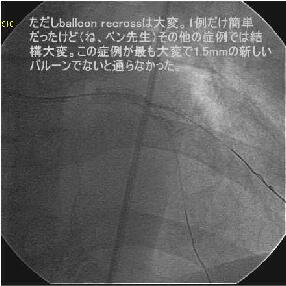

Crush���KBT.